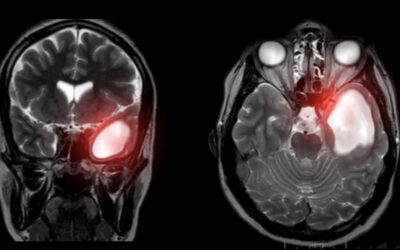

Son quistes no neoplásicos formados por aracnoides (tejido normal que cubre el cerebro). Pueden ser congénitos o adquiridos (ej.:por traumatismo craneal).

La localización es variada, siendo más frecuente en: fosa media (49%), ángulo pontocerebeloso (11%), región selar y supraselar (10%) y fosa posterior en región vermiana (9%) e interhemisférico (5%).